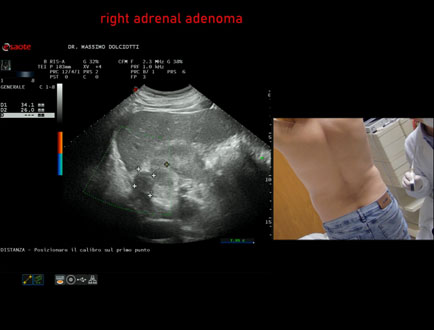

Età Paziente: M 49 anni

Motivazione dell'esame: riscontro occasionale

Commento all'esame: le immagini ed il video documentano in regione surrenalica destra, formazione ipoecogena a margini definiti, da ricondurre, come prima ipotesi, ad adenoma surrenalico.

Conclusioni: adenoma surrenalico destro (right adrenal adenoma).

In collaborazione: Dr.ssa Marica Manfredi - Ancona, Dr. Ilir Qose - Ancona

Presentazione: Dr. Massimo Dolciotti - Ancona